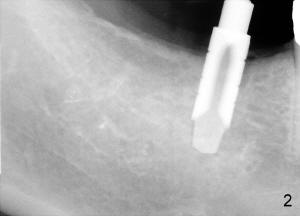

Mr. Lip returns to clinic for #30 and 31 implant placement. At the time of impression, there is no sign of gingival swelling around the tooth #19 (Fig.1: >; although the tooth has suspected root fracture). The patient requests keeping this affected tooth as long as possible while #30,31 implants are being placed and restored. This is not the case at the appointment of implant placement on the other side (Fig.1': *). There is localized gingival erythema and edema at the ML line angle. It appears that the treatment plan should be changed: the number of implants to be placed should be reduced from two to one and the infected tooth should be extracted to decrease the chance of implant infection. These two procedures are intended to be done at the same time so that bone harvested from #30 implant osteotomy (Fig.2) can be saved (Fig.2': < in dapen dish) and grafted in #19 sockets (Fig.3', 4'), particularly in the mesial one with severe bone loss due to root fracture.

The second precaution to be taken to prevent post-implant infection is to place implant subgingival (submerged with suture to close the incision), instead of supragingival (Fig.3,4). Bicon 5x8 implant is used with bone expansion. The short implant also reduces chance of damage to the inferior alveolar nerve. Paresthesia and hyperethesia (pain) prevents the patient from keeping good oral hygiene post-operatively.